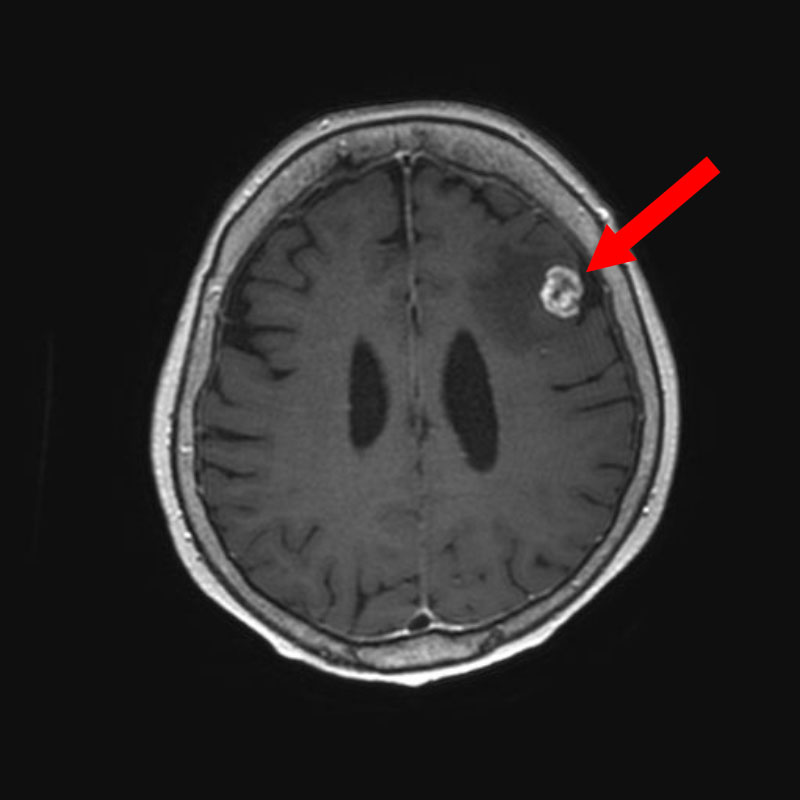

698

'25年11月

40代

右前頭葉腫瘍

頭蓋内腫瘍摘出術